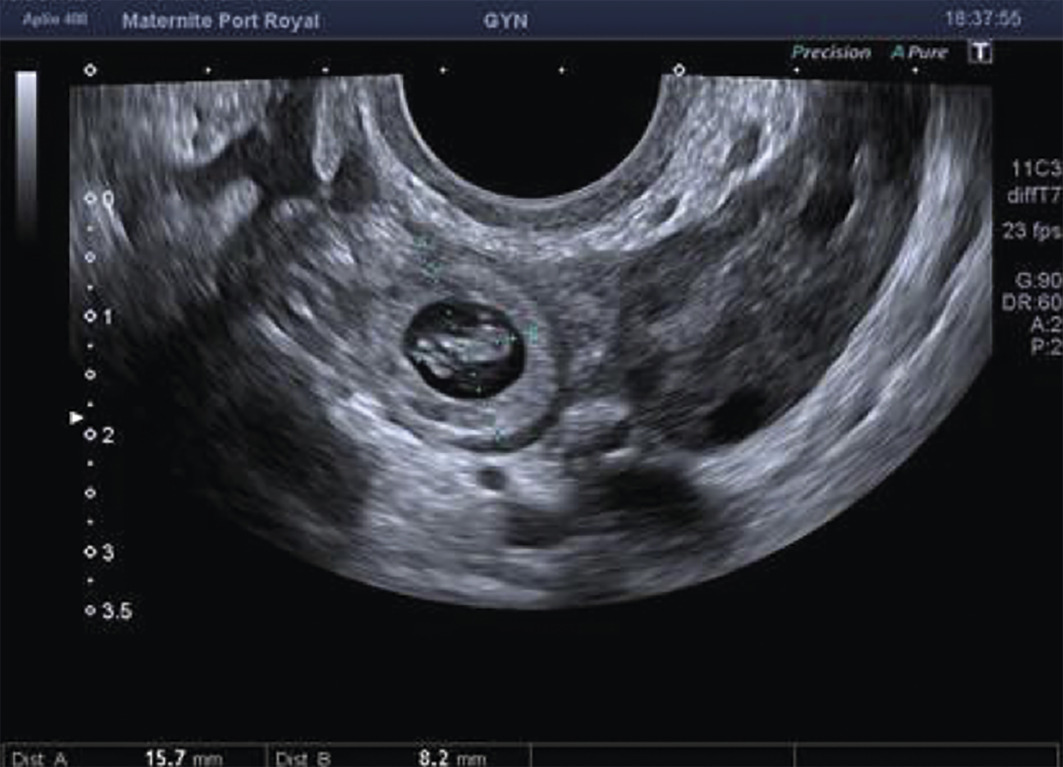

L’échographie, indispensable, doit examiner le pelvis mais aussi l’abdomen. Elle est donc réalisée par voie endovaginale, sus-pubienne et abdominale. On peut visualiser une masse latéro-utérine (fig. 1). Au sein de cet hématosalpinx, un sac gestationnel peut être visible, voire un embryon (fig. 2) ayant parfois une activité cardiaque positive. Le passage de la sonde à ce niveau est douloureux.

Souvent, le principal signe est indirect :

– vacuité utérine (fig. 3) et taux de hCG supérieur à 1 500 UI/L, fortement évocateurs. En cas de métrorragies, une lame d’hématométrie peut être visible en intra-utérin (« pseudo-sac gestationnel » : image hypo-échogène centrée dans la cavité, sans couronne trophoblastique) ;

Remerciements au Dr Gilles Grange, maternité Port-Royal, Paris pour les figures 1, 2 et 3.